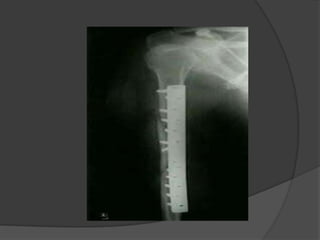

CASE 1

IMPLANT FAILURE   POST OP X RAY